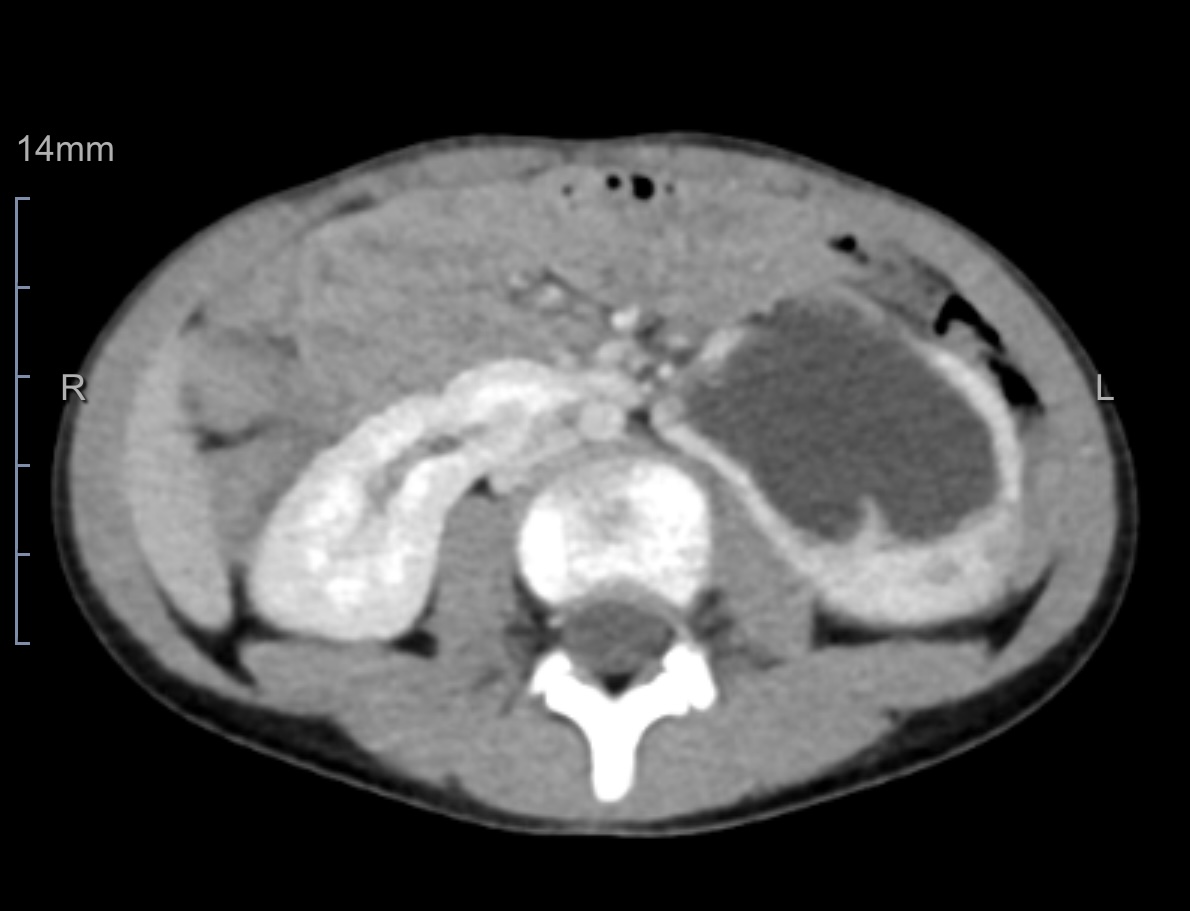

据了解,患儿依依(化名)多月来反复出现不明原因的腹痛及呕吐,经仔细检查后,被确诊为先天性马蹄肾——一种因两侧肾脏在下极融合导致的罕见结构异常,常伴随肾脏旋转不良及血管变异。该多发畸形已造成其左侧肾脏严重积水,若不及时干预,将进一步损害患儿依依的肾功能,甚至需切除肾脏。

面对这一复杂病情,医院启动了多学科协作机制,由小儿外科和泌尿外科团队共同研究影像资料,结合患儿具体情况,为其制定了个性化的微创手术方案。

手术中,在麻醉科团队的配合下,运用达芬奇机器人手术系统成功离断马蹄肾峡部,解除异位血管对输尿管的压迫,纠正了旋转不良的左肾,从而有效解除梗阻,最大限度保留肾功能。手术过程顺利,出血量少,患儿术后恢复良好。最新超声复查结果显示,依依的肾积水已明显减轻,其腹痛症状完全消失,目前已恢复正常学习和生活。